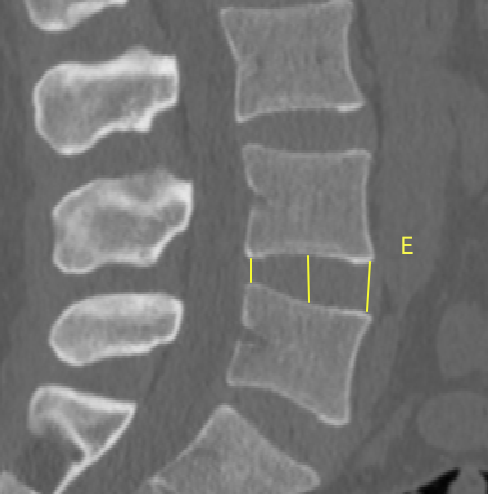

2�����、通过术前CT测量L4-5节段手术部位的(1)上位椎体后下角水平方向到关节突关节的距离(A)��;(2)纤维环后缘的中点水平方向到关节突关节的距离(B)���;(3)下位椎体后上角水平到关节突的距离(C)��;(4)上位椎体的椎弓下切迹与下位椎体椎弓上切迹连线的距离(D)���,图 6����;(5)在手术节段的棘突矢状位CT层测量椎间隙高度(E)����,图 7�����;(6)在手术节段的关节突关节横截面CT层测量关节突间距离(F)����,图 8���,再通过术中及术后CT判断患者椎间孔成型级别���,将A-F测量数据与5级成型中的各级别成型进行相关性分析����。

图 7 E的测量方式 |